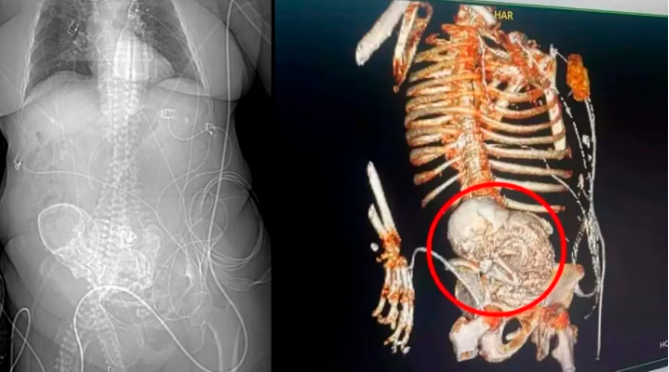

• Así se veía el feto calcificado en la tomografía. /FOTO: REDES SOCIALES

Así las cosas, los profesionales decidieron practicarle una tomografía, la cual reveló la presencia del feto, un fenómeno médico llamado litopedia.

Esta condición se denomina comúnmente ‘Bebé de piedra’, que es una afección poco común generada por un embarazo ectópico, en donde el óvulo fecundado se injerta fuera del útero. Luego de esto, se presenta la muerte del feto y su posterior calcificación.